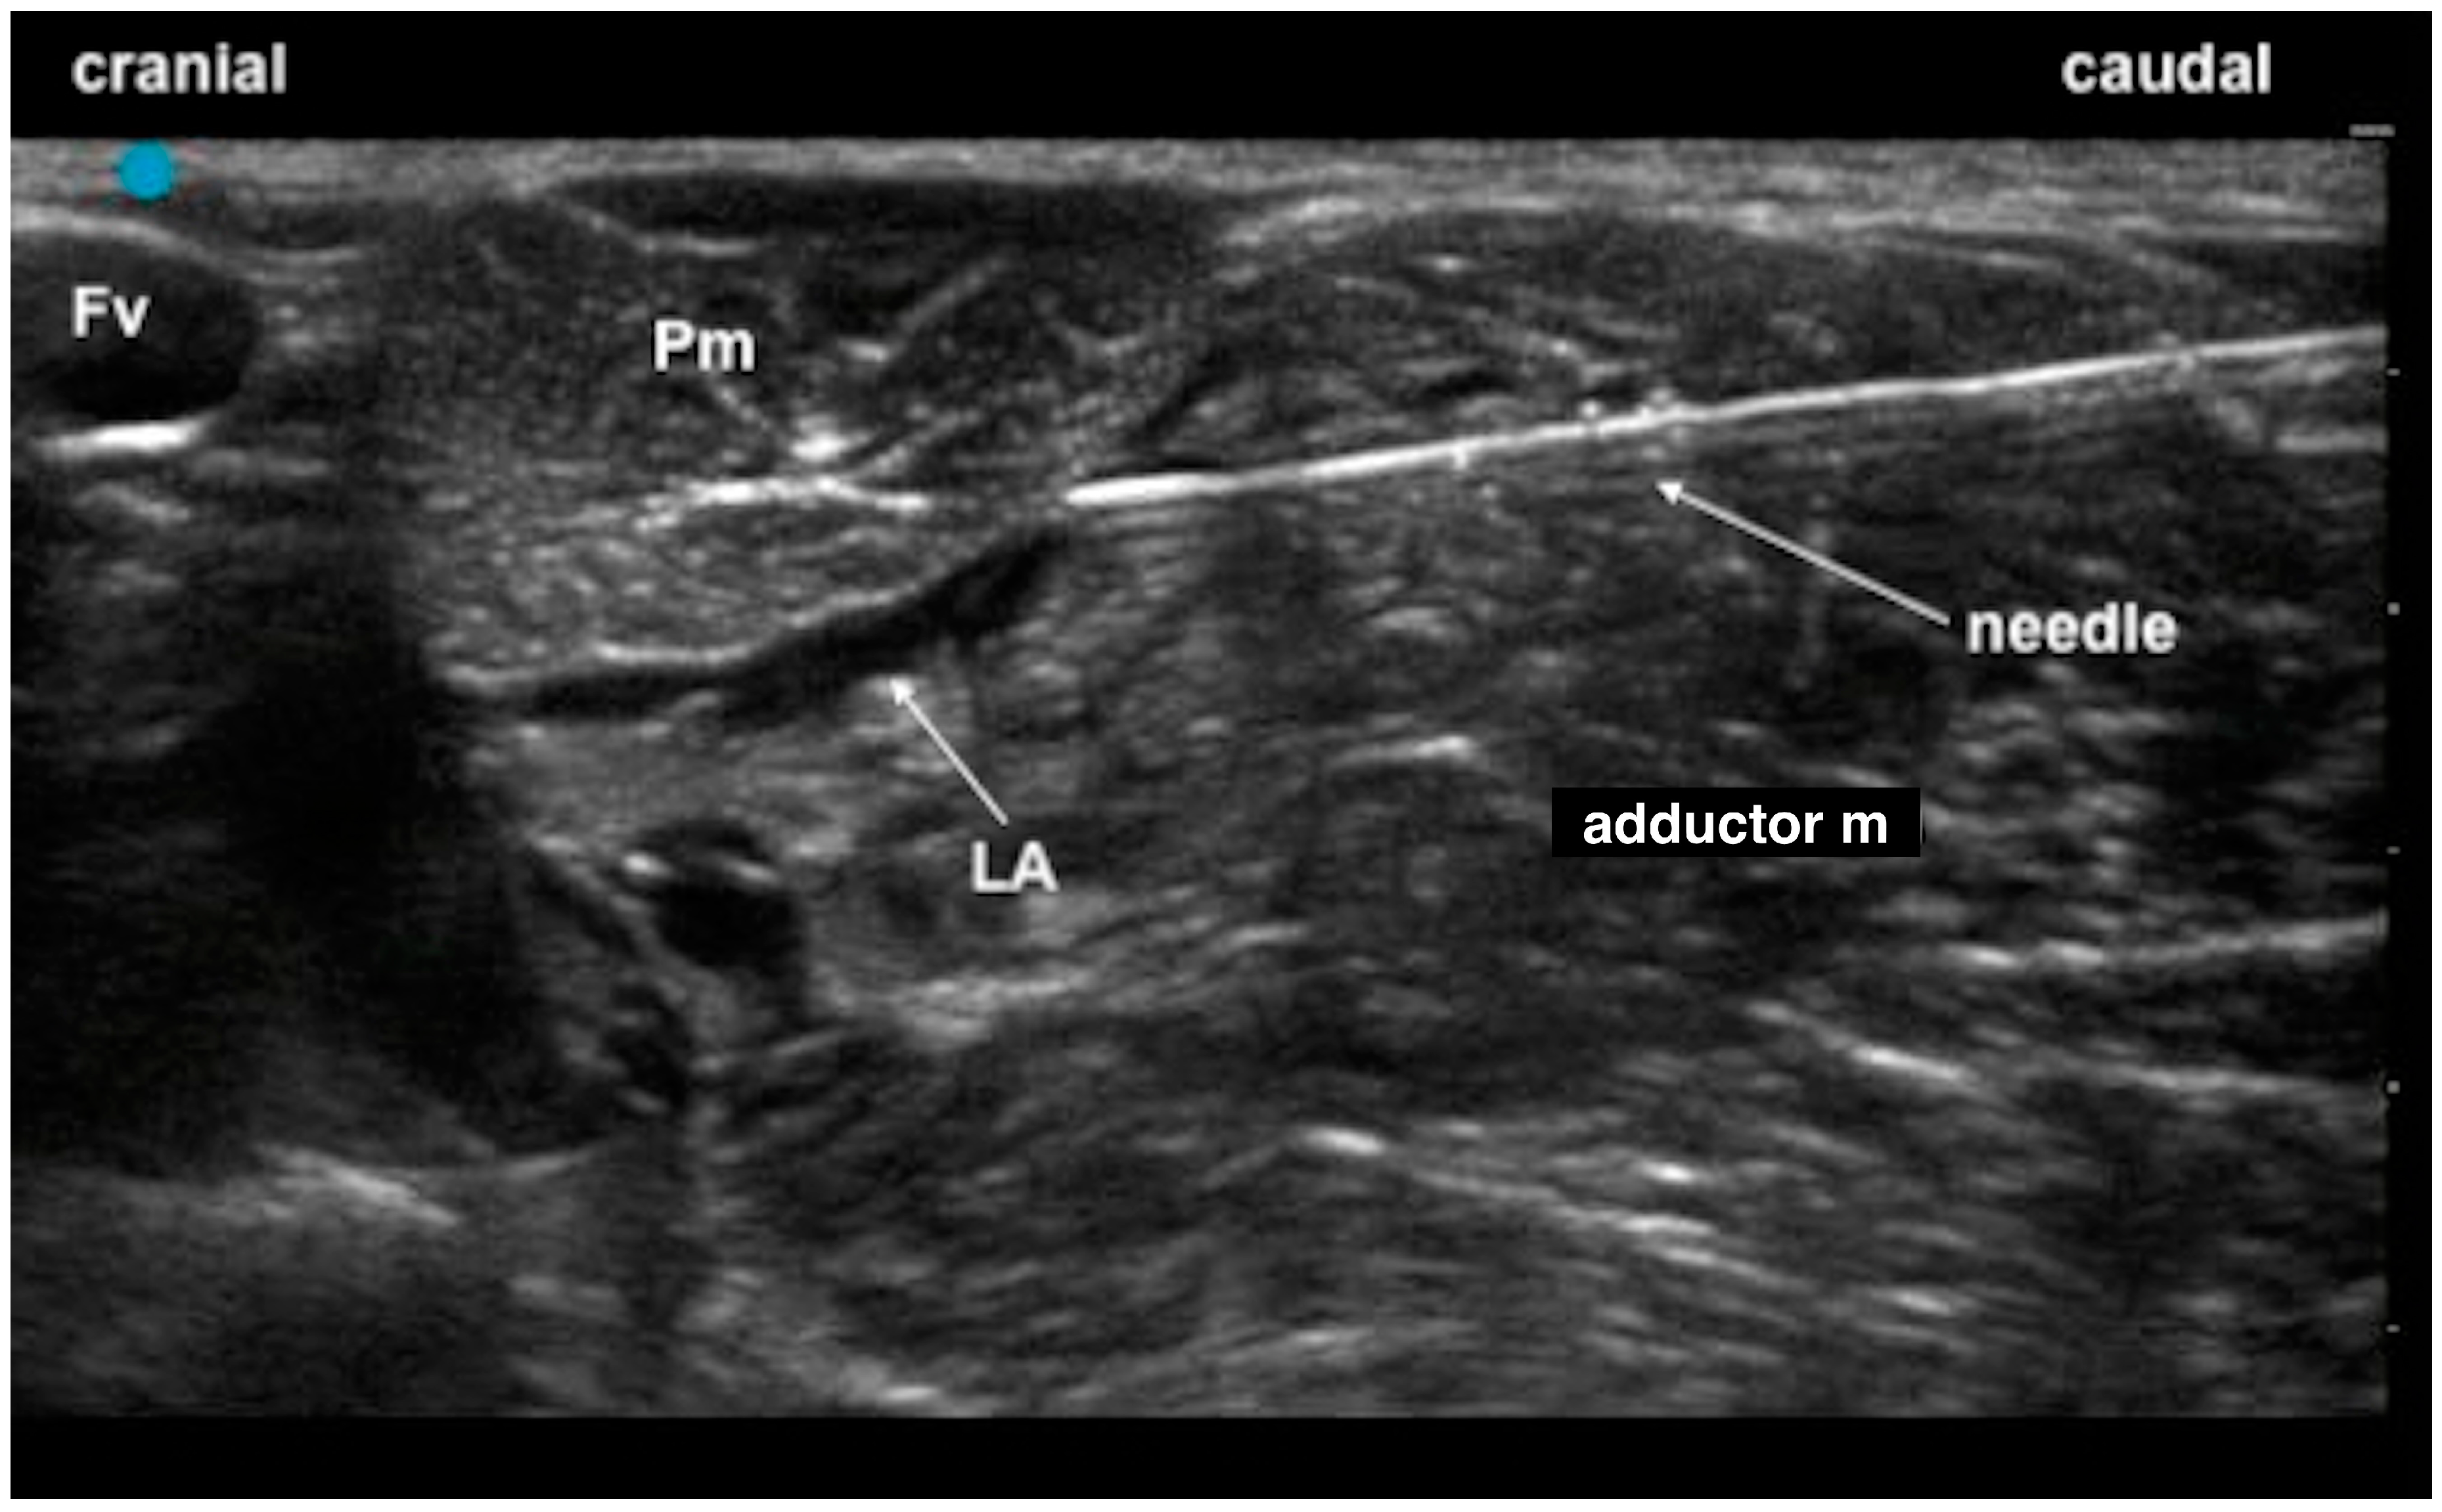

2.1. Phase 1: Anatomical Study

- Castro, D.S.; Garcia-Pereira, F.; Giglio, R.F. Evaluation of the potential efficacy of an ultrasound-guided adductor canal block technique in dog cadavers. Vet. Anaesth. Analg. 2018, 45, 566–574. [Google Scholar] [CrossRef] [PubMed]